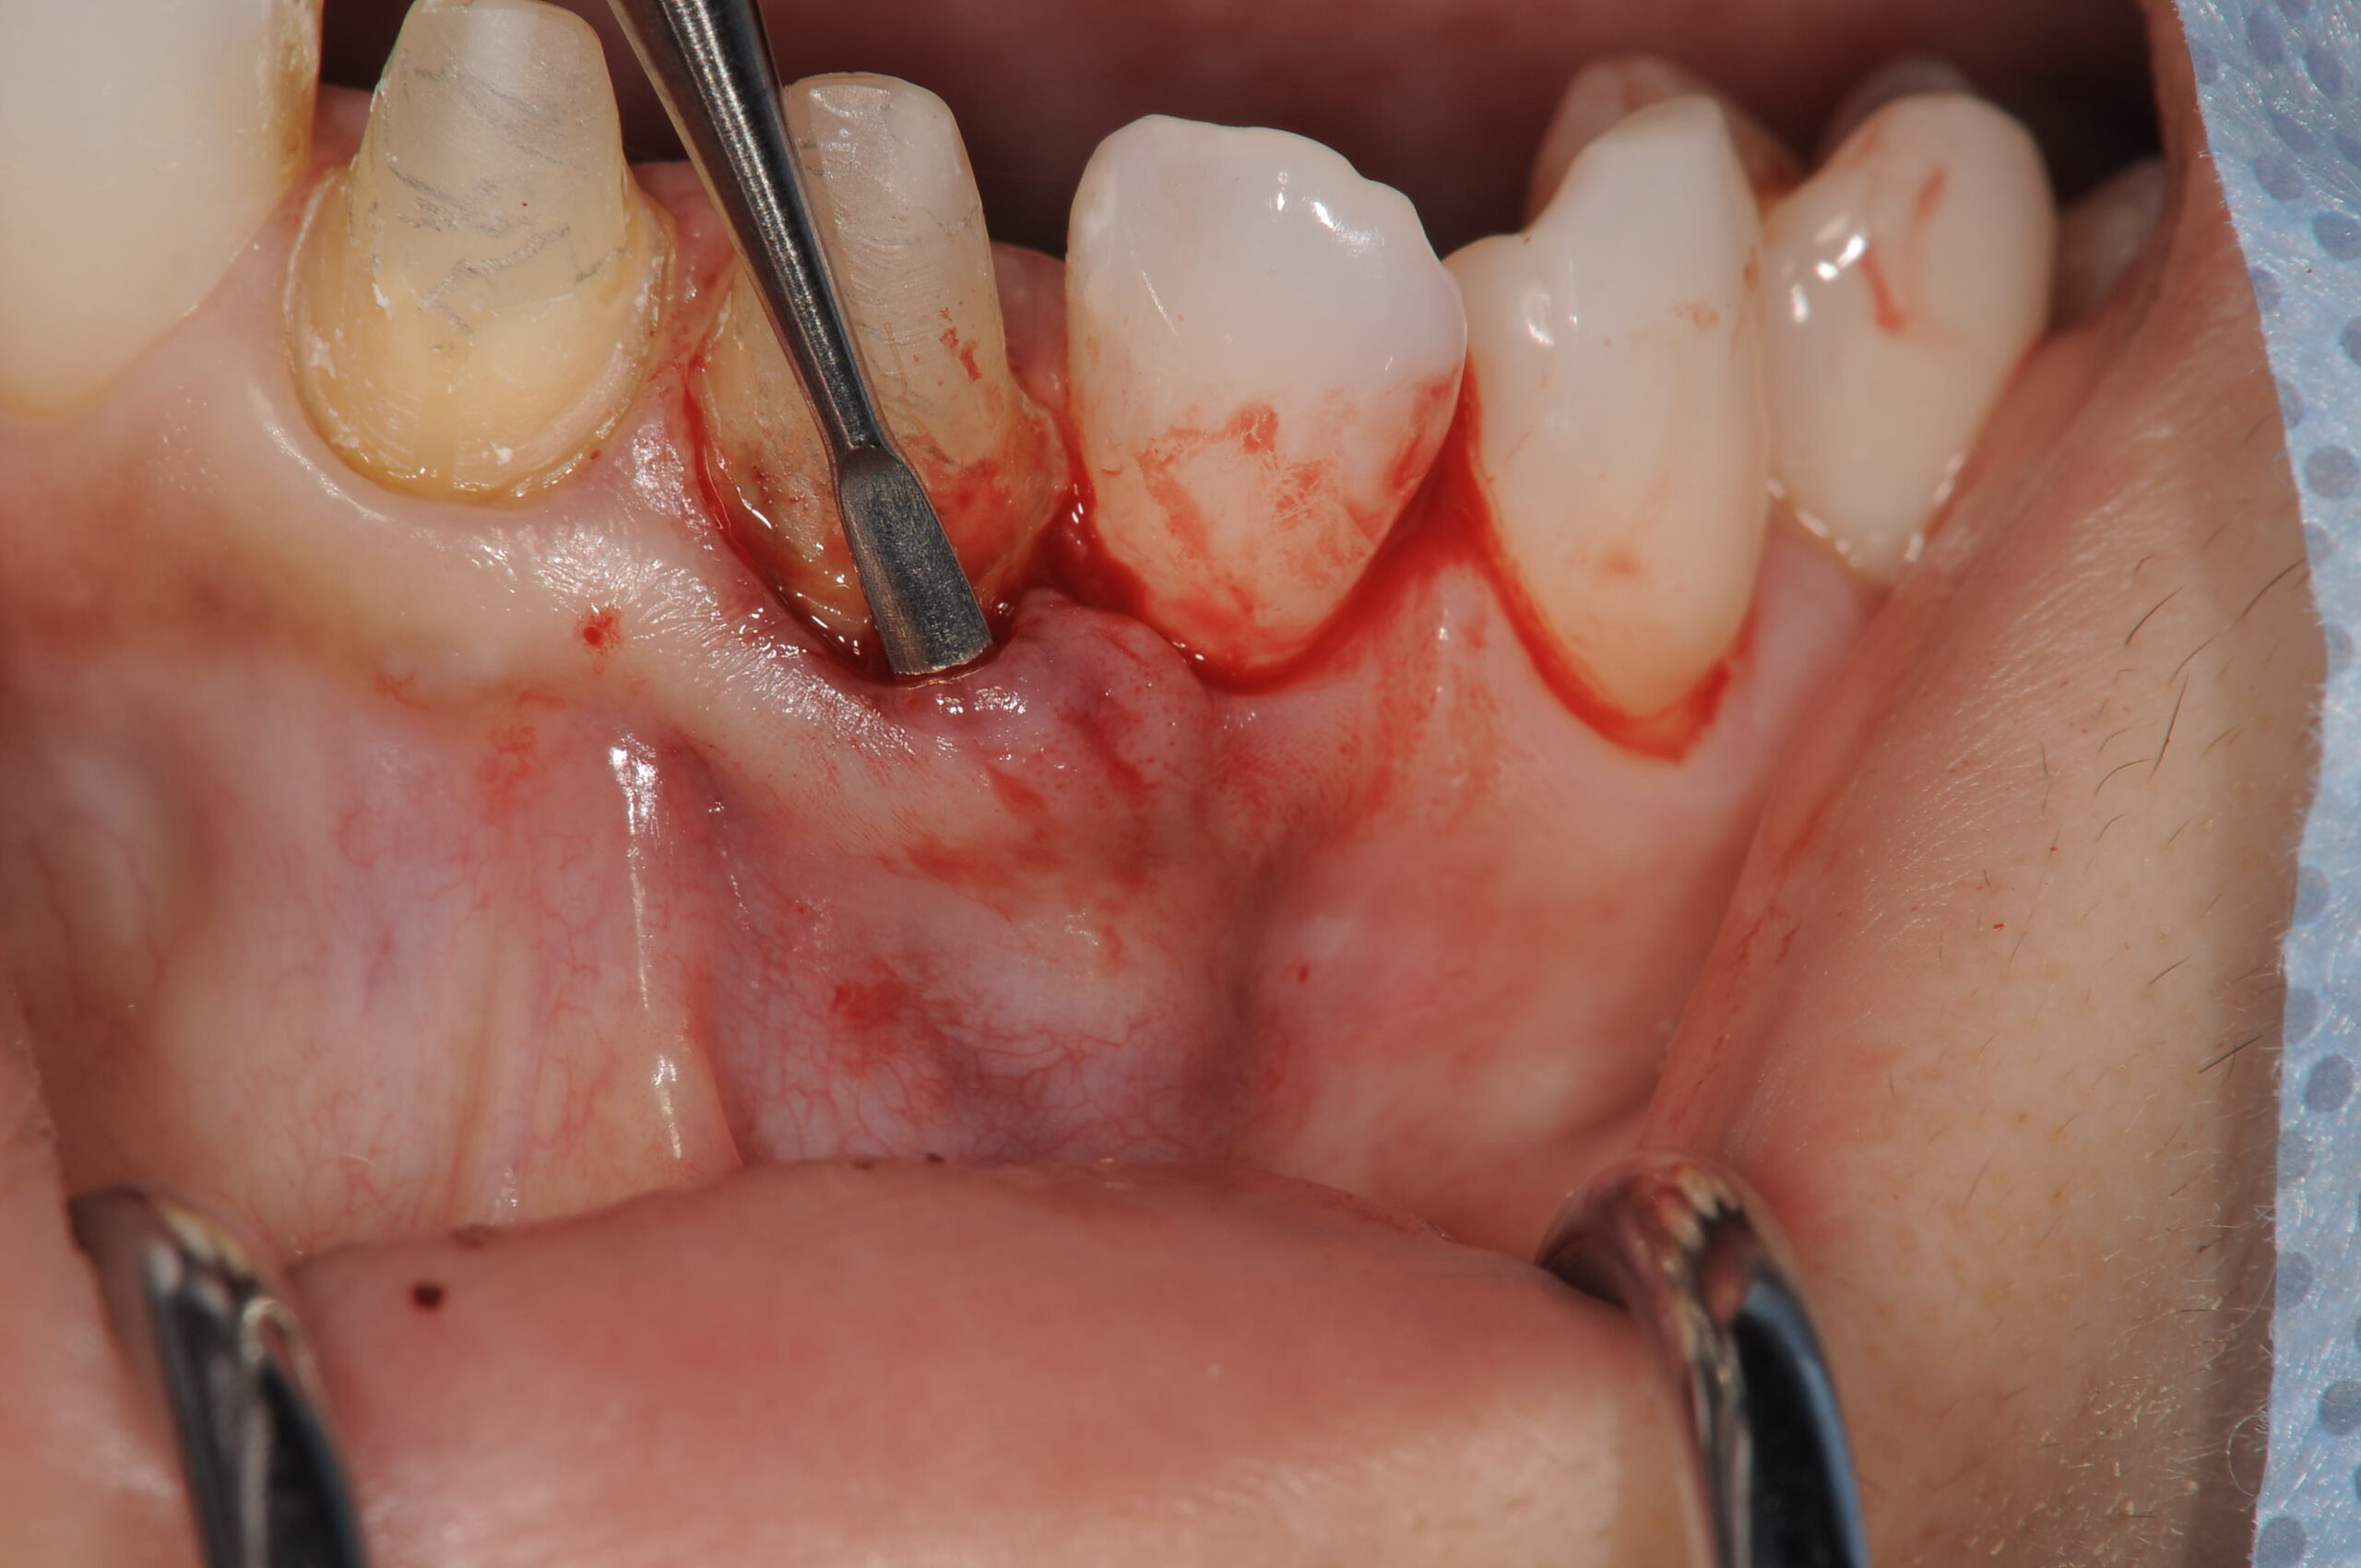

結合組織を移植する場所にトンネリングテクニックを行います。歯間乳頭の幅径がれば、口蓋側とつないだまま剥離しますが、ほとんど幅がないためやむを得ず切離します。